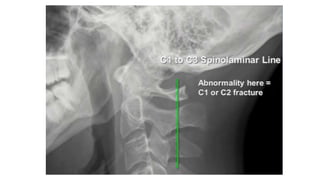

Spinal laminar line

• #23 Ant vert body line Post vert body line Spinal laminar line Line across the spinous process

• #24 Too wide or narrow or uniform Too wide or parallel Too wide too narrow